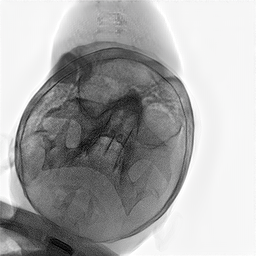

Refer to caption

Figure 2: Dataset overview. The synthetic domain contains Low and High dosage samples generated using the Mentice VIST® simulator; the real domain includes Low, Normal, and Exposure dosage categories acquired from a skull phantom using the Philips Azurion IGT system.

We develop and release a new dataset of real and synthetic head X-ray images, X-DigiSkull, to study the domain adaptation. The dataset consists of synthetic X-ray images of a human skull generated using the Mentice VIST® simulator 111https://www.mentice.com/simulator/vist-g7. Real‑time X‑rays are generated by holding the 3D voxel “patient” head model with per‑voxel attenuation, casting one ray per detector pixel to form a digitally reconstructed radiograph and then approximating scatter, focal‑spot and detector blur, grid/heel effects and detector response, adding quantum/read noise and final image post-processing as the C‑arm and devices move. Real images are acquired from a clinical-grade physical skull phantom using the Philips Azurion Image Guided Therapy (IGT) system. Images are captured from common IGT working positions for neuro procedures. The dataset consists of multiple orientations and is available in three different radiation dose settings: low, normal, and exposure (Philips exclusive), the latter offering enhanced image quality and detail, as shown in Figure 2. This consists of viewing angles rz[40,+40]r_{z}\in[-40^{\circ},+40^{\circ}], ry[40,+40]r_{y}\in[-40^{\circ},+40^{\circ}], rx[40,+40]r_{x}\in[-40^{\circ},+40^{\circ}] with respect to the starting position in 10 increments and up to 3 images at each position to capture the noise present. This results in a total of 2,187 real images. The coordinate systems of the real and synthetic environment are aligned and synthetic images are rendered to approximate the same viewpoints as the real phantom images with the patient table starting at a similar position.The head 3D model used in the simulation is meticulously built from a real clinical case. We capture the synthetic images in finer increments of 5 across the three angles, producing the 5,832 (18318^{3}) images 222Data available at https://zenodo.org/records/16535437. The aim of this alignment is not to achieve precise supervised image translation, but rather to establish a consistent reference structure that preserves spatial features. The composition of the dataset is summarized in Table 1, which contains information on the splits and the number of images available. All images are cropped and resized to 780×\times780 pixels. The test set is obtained by uniformly sampling 15% of viewing angles and corresponding images to ensure a representative distribution. For our experiments, we focus on the task of converting synthetic images at high dose to real images at normal dose.